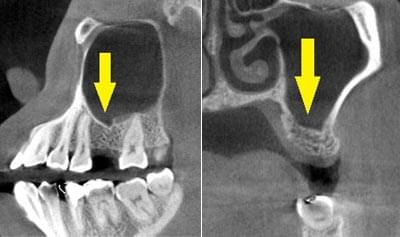

写真は患者様の治療前のレントゲン写真です。右上顎の大臼歯を喪失し、延長ブリッジを装着されていたのですが、支える歯が破折してしまい、抜歯が必要となりました。ここにインプラント治療を行うには、骨が薄くて、困難な状態でした。

CTで見ると、骨が薄いのが良く分かります。黄色の矢印の部分、白く写るのが骨で、矢印のある黒い部分が上顎洞という空洞です。

この空洞部分に、人工骨を入れて、閉鎖しておくと、数か月ほどで骨に置き代わっていき、インプラントを埋入できるだけの骨量になります。サイナスリフトが終了して、数か月経過し、薄かった骨が十分な厚みができたCT画像です。黄色矢印の部分、白く写る骨が増えています。